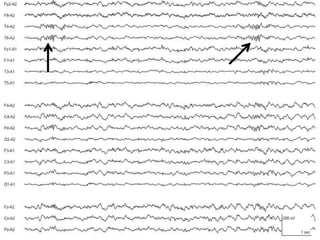

Wicket waves

• Short runs of 6-11Hz spikes, sometimes single spike

– usually within alpha frequency range

• Monophasic arciform waveforms (60-200uV)

• Anterior or mid-temporal region

– Usually unilaterally,shifting emphasis between sides

• Sharp monophasic, no slow wave

• Present in relaxed wakefulness, drowsiness, light sleep

• Usually in middle and late adulthood

• Clinical significance: analogue of the auditory alpha rhythm

– May decrease with auditory stimulation

– Not associated with epilepsy

Benign Sporadic SleepSpikes BETS–Benign Epileptiform Transients of Sleep • Occur in light sleep (non-REM 1 and 2 sleep) • Amplitude of <50 microV and duration of <50 ms • Usually monophasic, occasionally diphasic • Located temporal uni- or bilateral • Incidence of 20% • Small sharp spikes are not associated with epilepsy